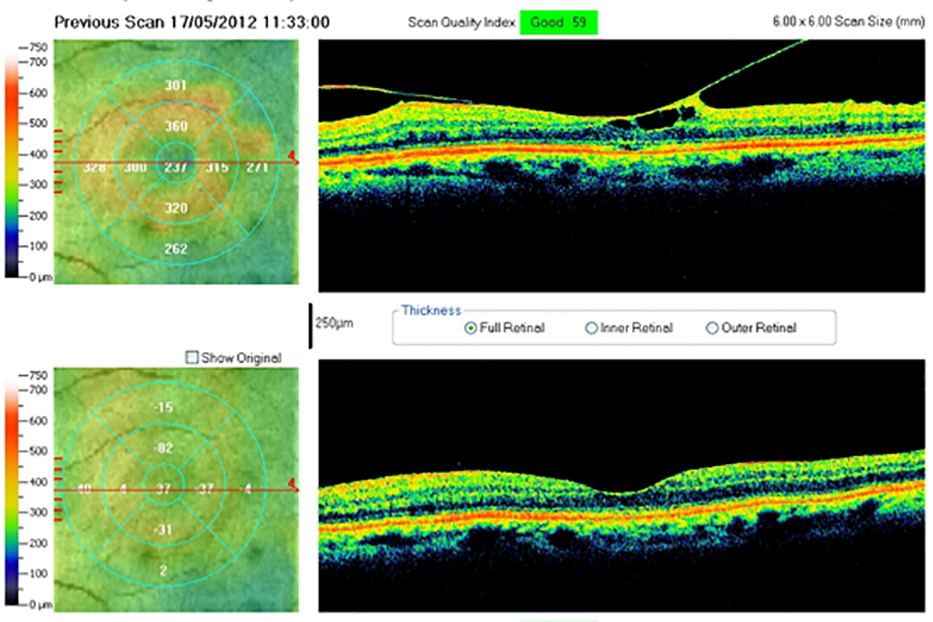

La membrana epirretiniana (es decir “membrana sobre la retina”) o en sus etapas avanzadas llamada pucker macular , es una patología del ojo consistente en el desarrollo de una sutil membrana casi translúcida sobre la mácula (es decir, la zona central de la retina que es el sector fundamental para la visión). Cuando tal membrana se contrae y se arruga causa una deformación y una progresiva distorsión de la mácula misma con los consecuentes defectos visuales.